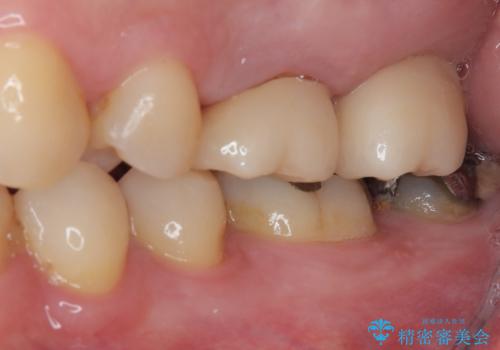

- 奥歯のむし歯と放置したむし歯を気にして来院された患者様です。

奥の歯は抜歯が必要なため、インプラント埋入による補綴治療を行うこととしました。

手前の歯は状態は良くないものの、抜歯するほどではないと判断したため、根管治療後にオールセラミッククラウンにて補綴治療を行うこととしました。